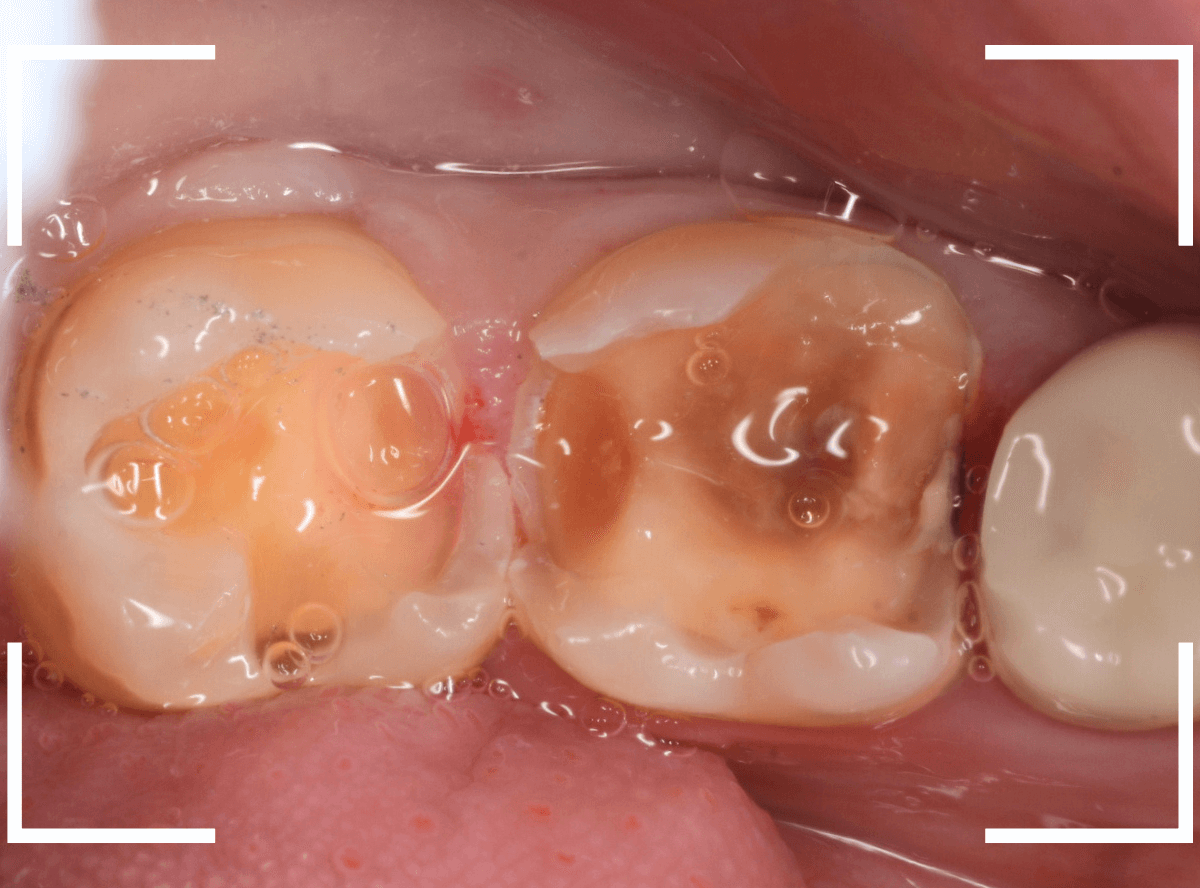

Case.22 痛みはないけど、歯のすきまから大きな虫歯

上の小臼歯の間が虫歯になっていた患者さんです。

症状はありませんし、見た目からも虫歯があるかはわかりませんでした。

治療を開始します。

少し削ると、中からすぐに虫歯が出てきました。

ある程度、虫歯を除去したところで、う蝕検知液で確認します。

赤く染まっている部分が虫歯です。

まだまだ虫歯が中で残っている状況で、かなり深い虫歯なのが確認できます。

全ての虫歯を除去しました。

レントゲン写真からある程度確認出来ましたが、歯の神経スレスレまで虫歯が進行していました。

ここまで虫歯が進行していても、全く症状を感じない事も多いです。

そして、ある時急に痛みを感じるのです。

虫歯は急に進行しません。

治療後の定期検診で確実に食い止めましょう。